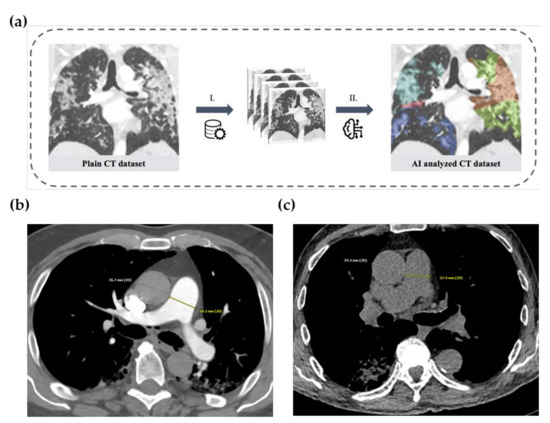

2.2. Image Acquisition

2.3. Artificial-Intelligence-Based Quantification of Lung Involvement

| CT Features on Admission | |||

| CT-Severity Score **** | 15 | (11–20) | |

| CT-Percentage of Lung Involvement **** | 36 | (20–57) | |

| Pulmonary artery to ascending aorta ratio | 0.86 | (0.78–0.94) | |